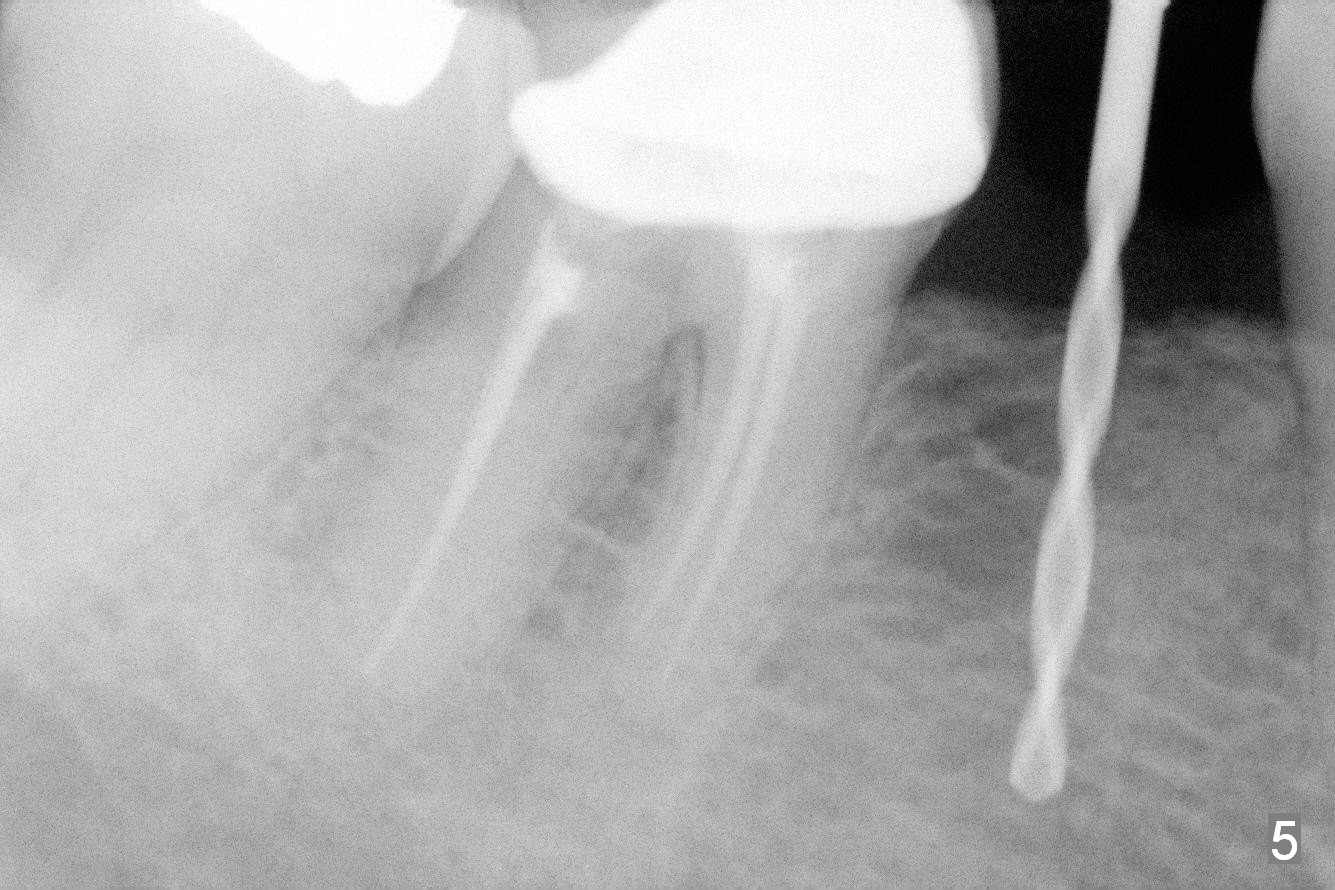

Preop photo shows the distal inclination of the tooth #28 (Fig.1). The distal surface of the latter is reduced before incision for implant placement at #29 (Fig.2). The buccolingual width is approximately 4 mm, as compared to 3 mm implant positioner (Fig.3). After 1.2x10 mm osteotomy (Fig.5), the mesiodistal cortical bone is removed with a small high-speed fissural bur (Fig.4). When a 2.5x12(2) mm 1-piece implant is placed (Fig.6), there is no buccal (Fig.7) or lingual plate perforation. There is no postop paresthesia. There is mild bone loss distal 4 months postop (Fig.8 *). Take photos before and after permanent crown cementation to show increase in ridge width after bone graft and improvement in gingival health after provisional modification. Take PA and/or BW post cementation to show that the distal bone resorption (Fig.8 *) is partially due to angulation. No continuous bone loss 15 months post cementation (Fig.9). There is mild bone resorption mesially 2 years 3 months post cementation (Fig.10). The soft and hard tissues remain healthy 4 years 3 months post cementation (Fig.11,12).